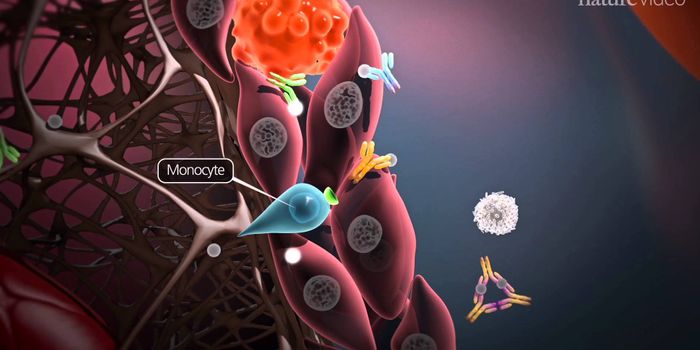

NOV 01, 2017VideosCells in the body have developed a variety of strategies toward removing harmful bacteria from the body. Phagocytosis is ...